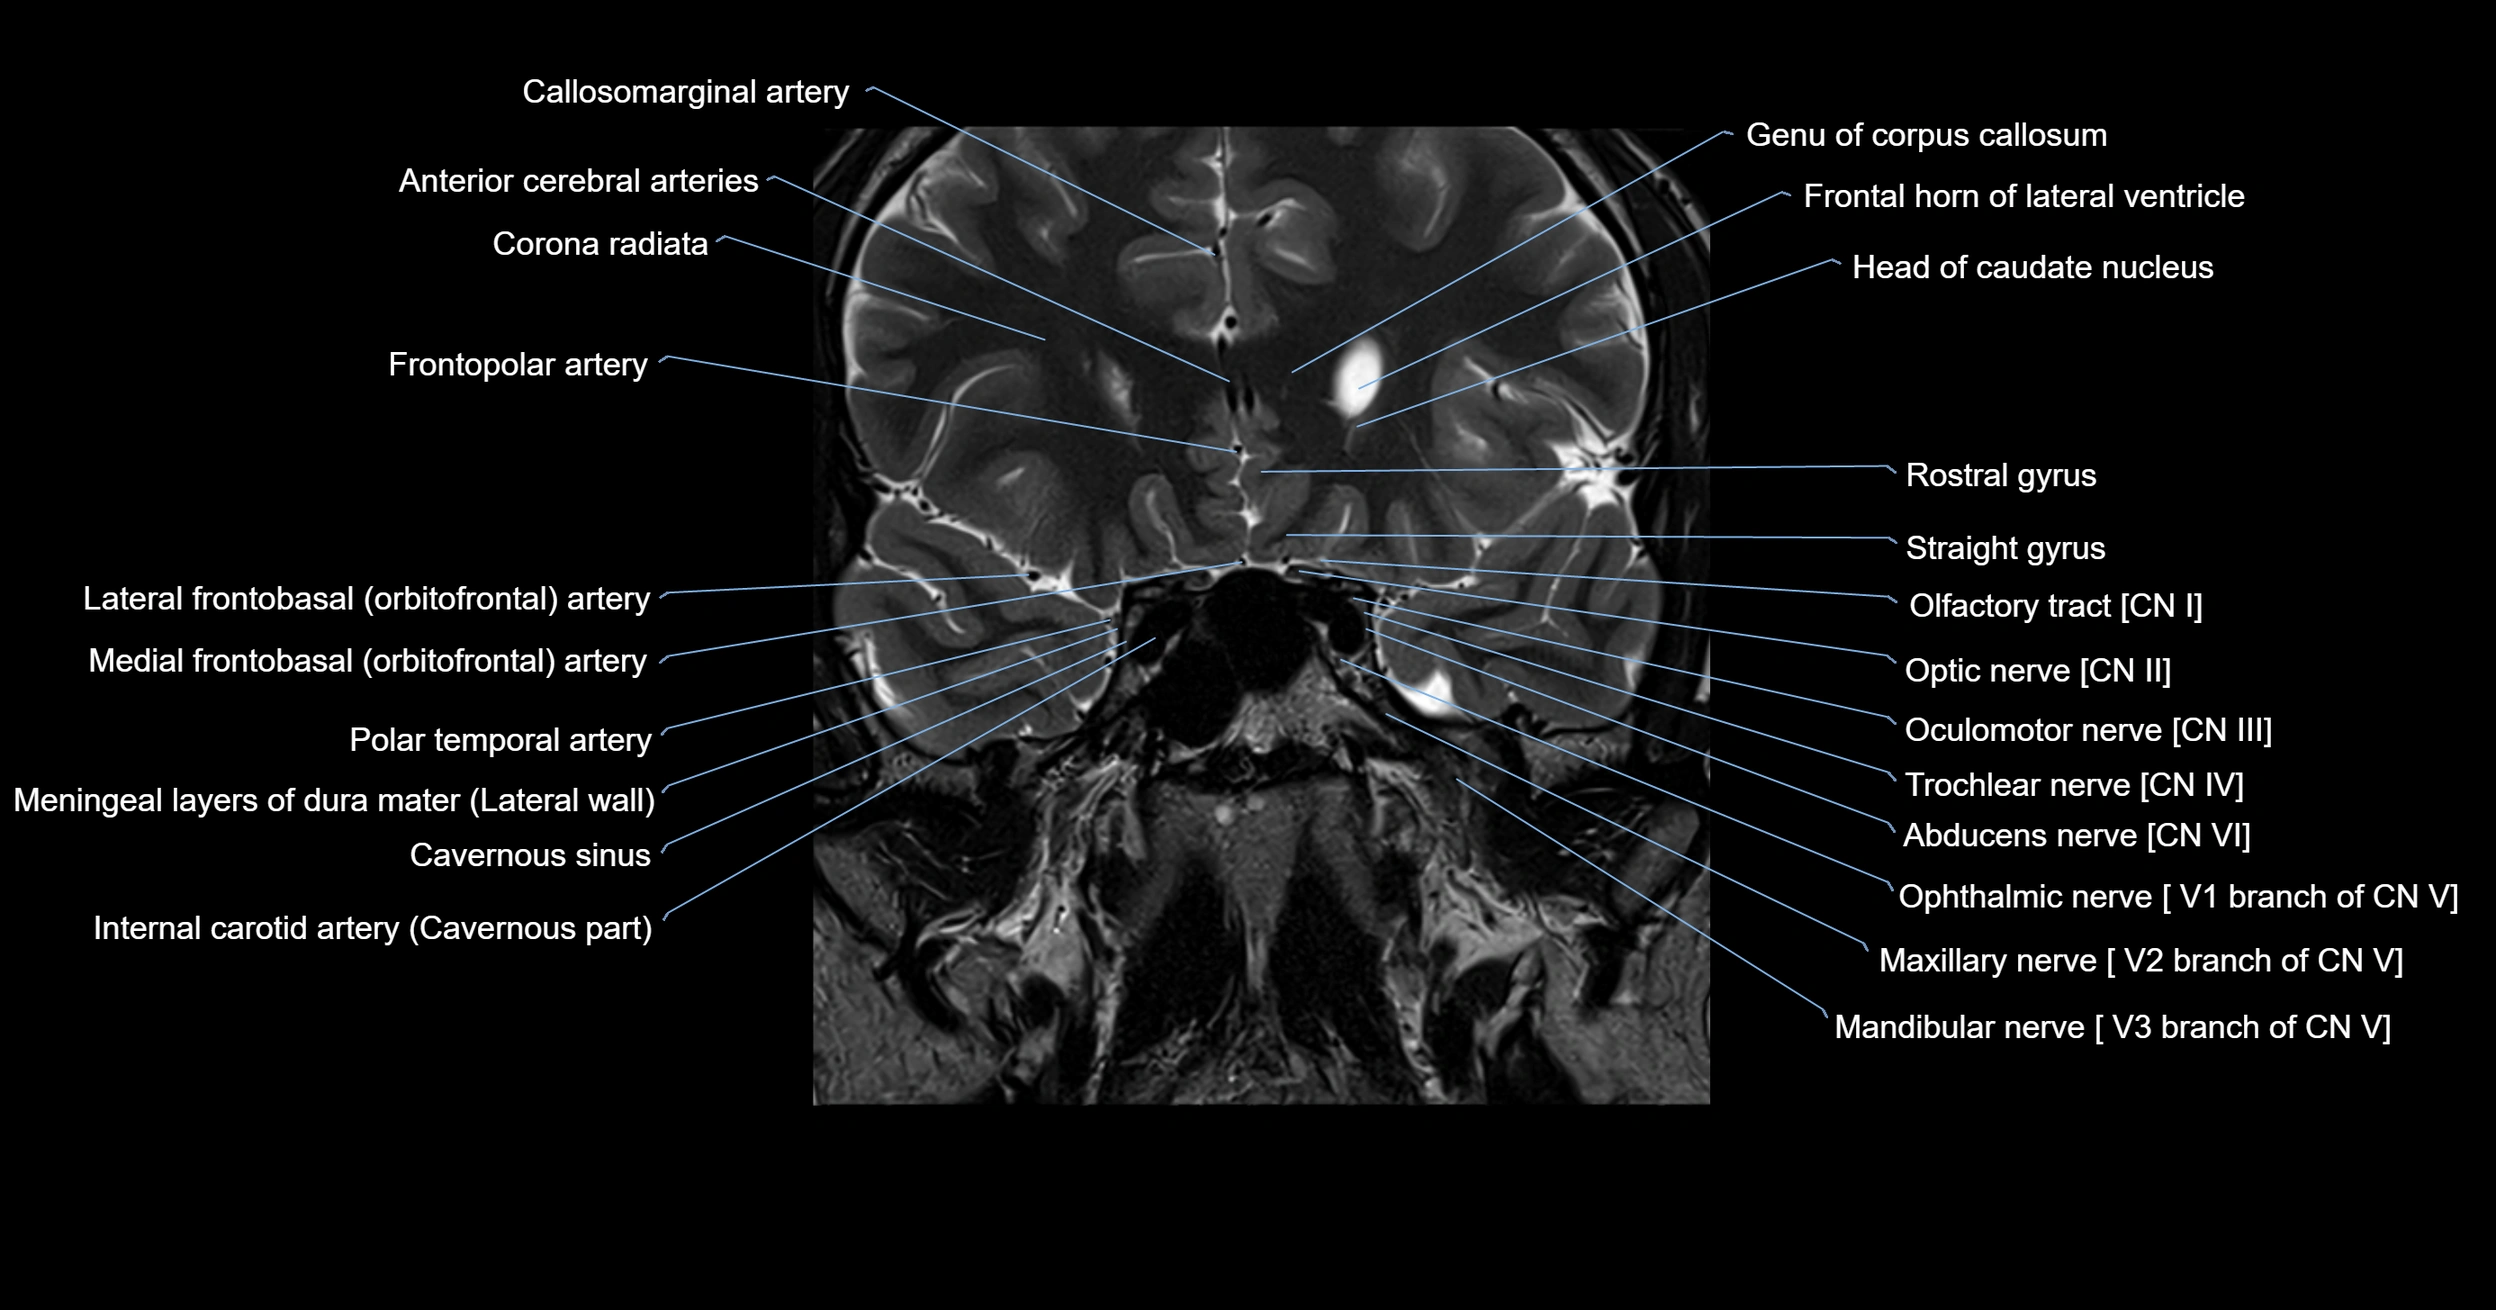

MRI images